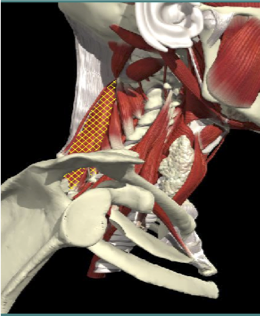

ACCURACY OF MUSCLE LOCALIZATION

- Muscles deep

- Not easily identified by surface landmarks

- Not palpable on examination

ACCURACY OF LOCALIZATION - SCALENES

ACCURACY OF LOCALIZATION LEVATOR SCAPULAE

LOCALIZATION OF MUSCLES IN DEEPER LAYERS

Layer 1

Layer 2

Layer 3

Splenius Capitis

Semispinalis Capitis

Longissimus Capitus

Semispinalis Cervicis

ACCURACY OF LOCALIZATION – DEEPER LAYERS

INJECTION SITES